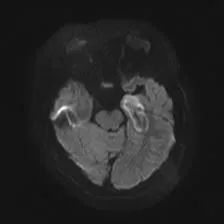

入院后,任杰主任对熙熙既往病史、治疗情况、症状学、影像学及检查结果等进行了详细了解,同时完善相关检查后,确诊为「症状性癫痫」,致痫灶为左侧颞叶内侧杏仁核海马硬化。

核磁检查提示明确的左侧海马硬化,病灶位于左侧颞叶,位置较浅,而且面积较小,传统的开颅手术切除对患者损伤大,相比之下,机器人及磁共振引导下激光间质消融术,术中既能实时观察到消融范围等毁损情况,达到消融病灶的目的,又对患者损伤又小,手术风险更低。

术前检查

「手术室」里做核磁随后,熙熙在术中磁共振室,先扫描确认激光光纤植入位置,随后在 MRI 实时颅内温度监控下,顺利完成了癫痫灶的激光消融治疗,治疗时长仅 5 分钟。可见消融范围与目标靶区吻合,周边结构无损伤,床旁拔除光纤即结束全部治疗,头皮仅有一处约 3 mm 大小创口。